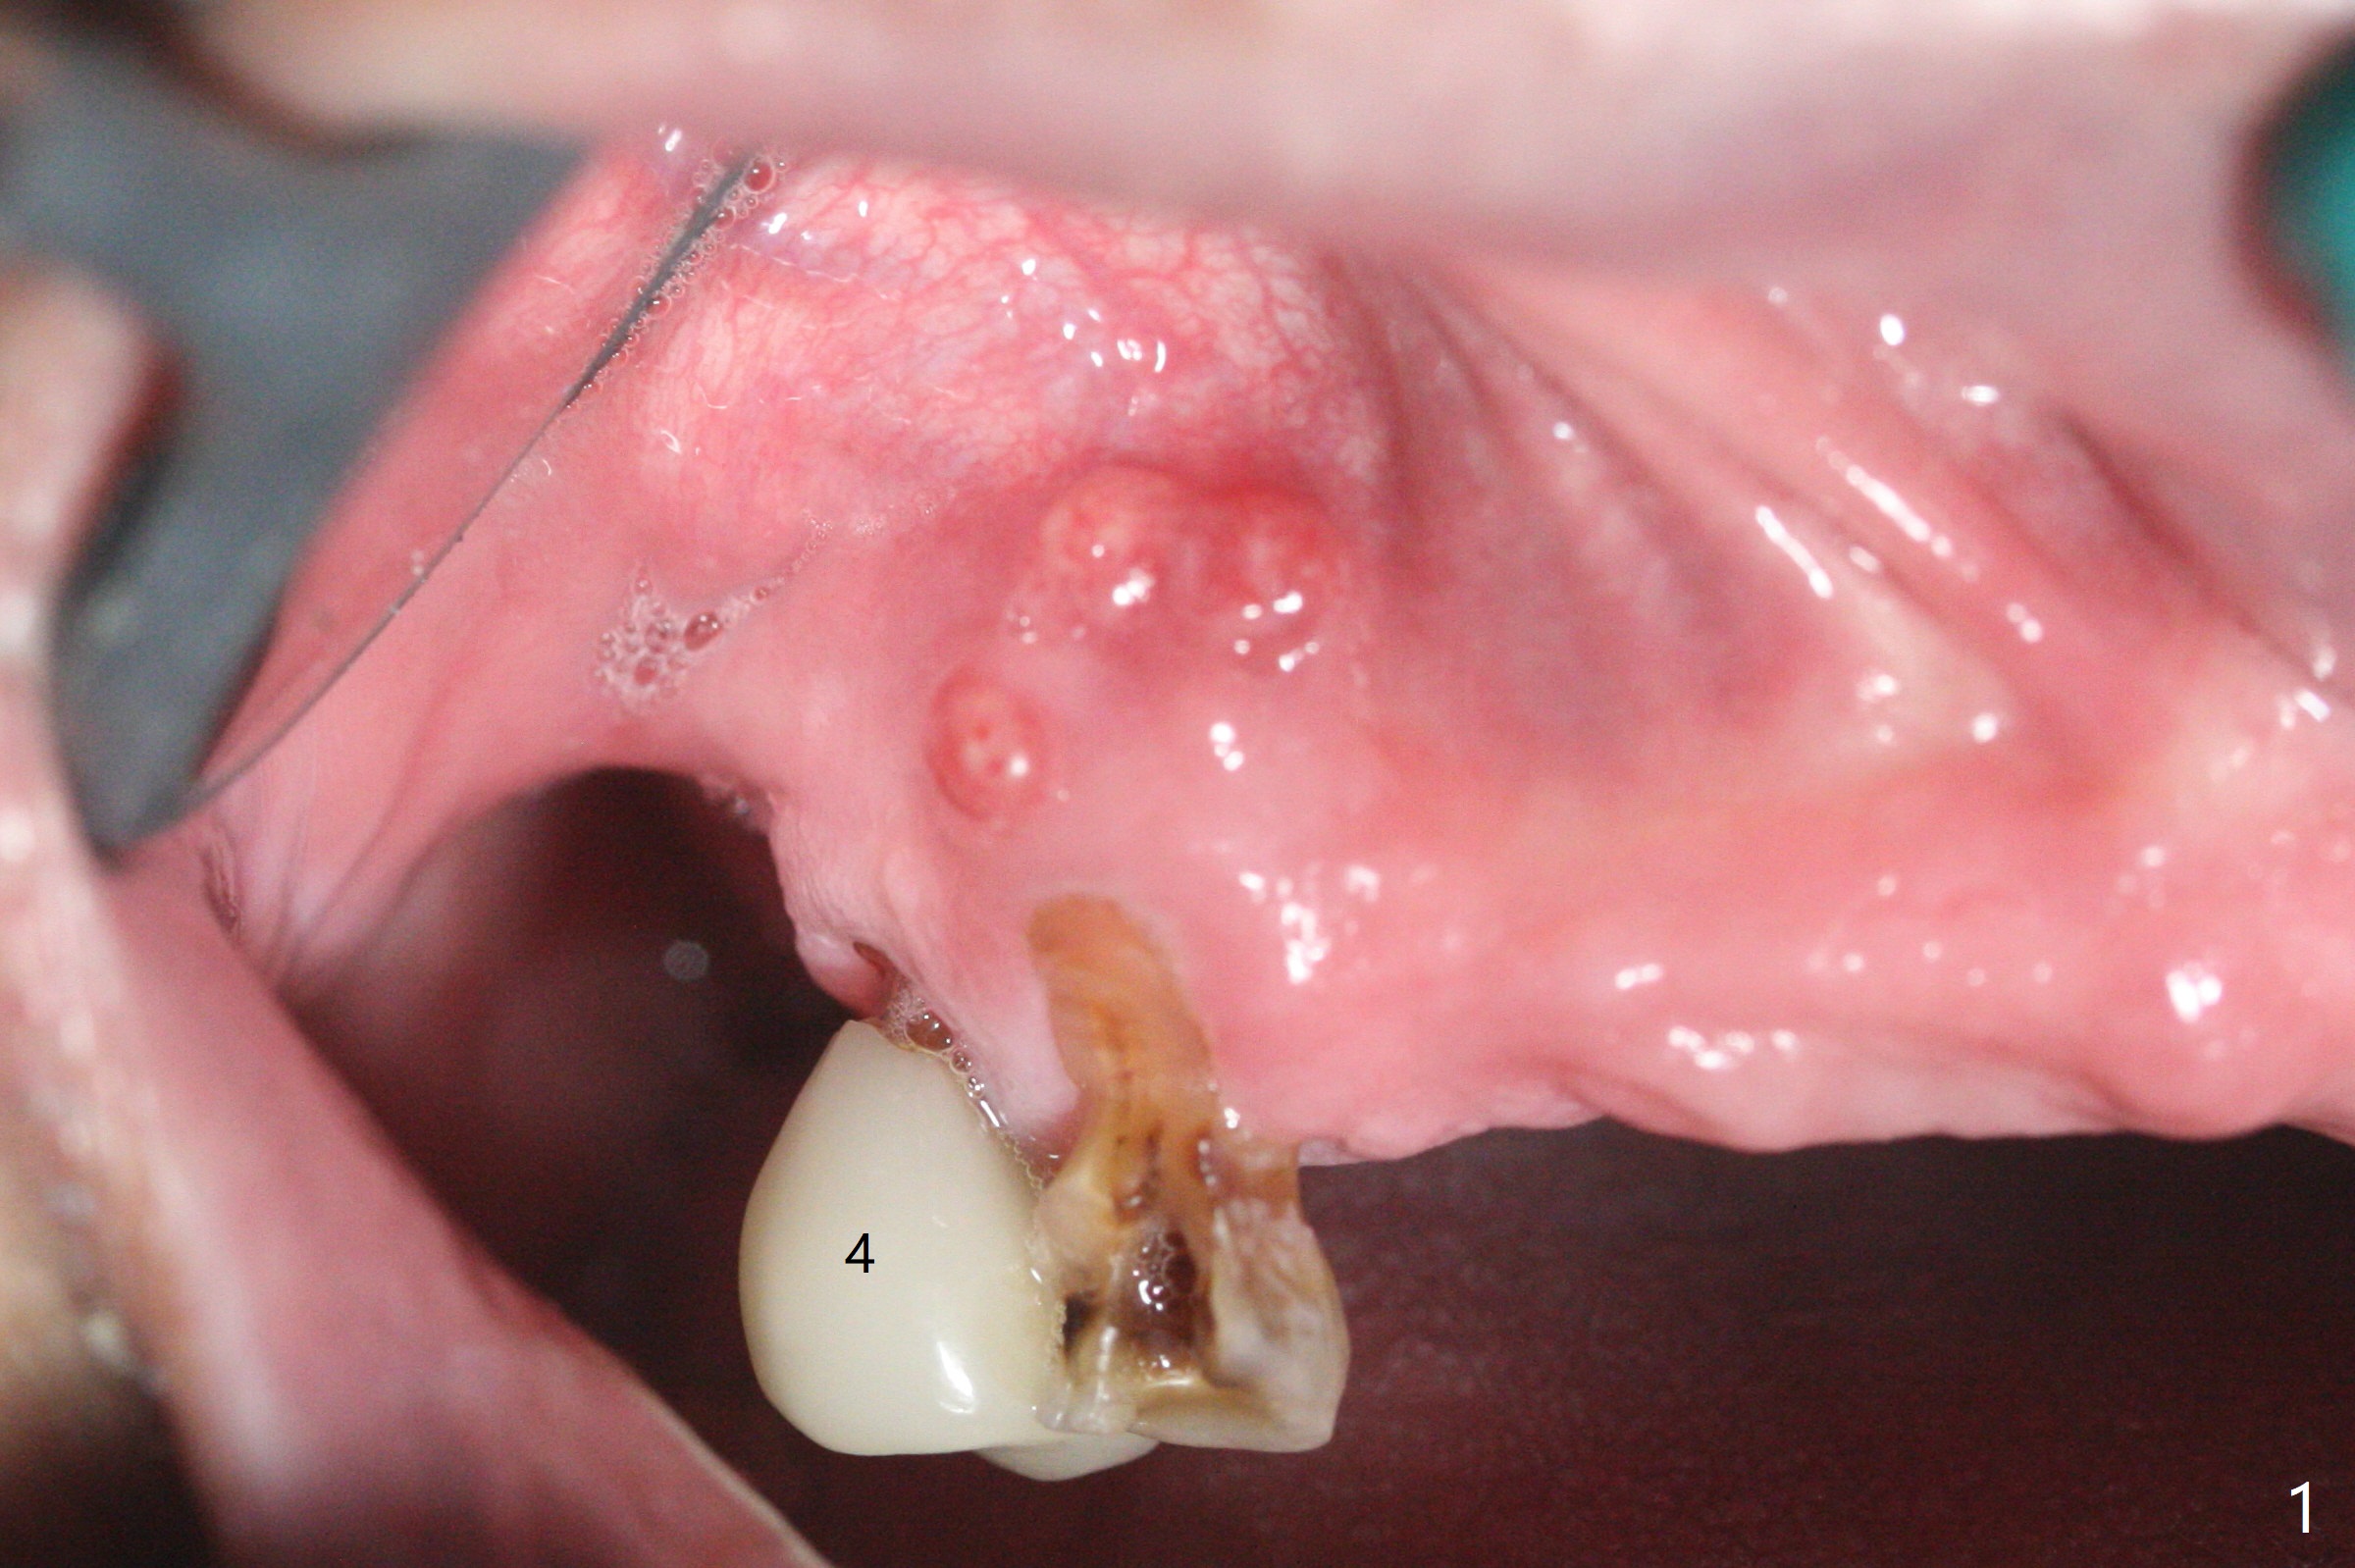

部分断裂的5号牙颊侧根尖有3个瘘道(图一),五类(颈部)缺损,严重牙龈退缩。牙齿拔除过程中断裂,需要手机切断拔除,颊侧骨板缺失,钻洞起源于牙槽窝腭侧(融合根,图二,五),植入4x13毫米长植体,根尖骨大约4毫米,植体也卡入近中,远中骨壁,扭力大于35Ncm,即刻放置基台,颊侧间隙(图三至五:*)放入粘性骨粉,牙槽窝口用PRF穿过基台关闭(图五),接着制作临时牙冠(图六:T),多次衬里严密关闭牙槽窝,而咬合面低,最后插入活动托牙(图七:RPD,左侧有两个基牙)。Return to Protect Graft Torque Xin Wei, DDS, PhD, MS 1st edition 05/18/2021, last revision 05/18/2021